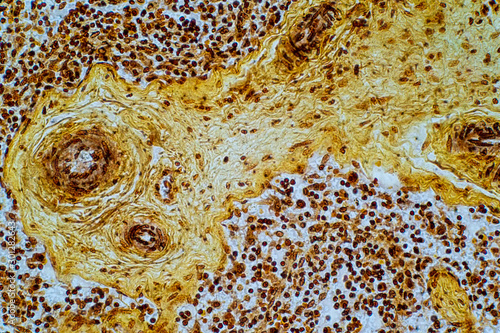

Mikrofotografi - Plakater, Poster, Billeder på lærred